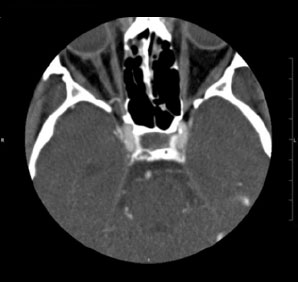

Tomografía computarizada Silla Turca

< Volver a "Tomografía Computarizada (TC) con Inteligencia artificial"Está indicado para el estudio de la glándula hipofisaria, que se aloja en una porción de la base del cráneo que llamamos silla turca.

Normalmente para la correcta realización de este estudio es necesaria la inyección por vena de contraste yodado, que nos aportará una mejor caracterización de la glándula.